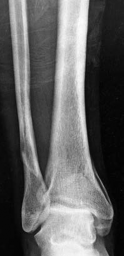

Partial articular fracture—plate fixation Case description A 53-year old man injured his right ankle in a mot…

Tibial shaft fracture extending into the plafond—intramedullary fixation Case description a A 25-year-old wom…

Tibial shaft fracture extending into the plafond—plate fixation Case description A 26-year-old man fell from …

Metaphyseal fracture with joint involvement Case description A 38-year-old woman was involved in a motor vehi…